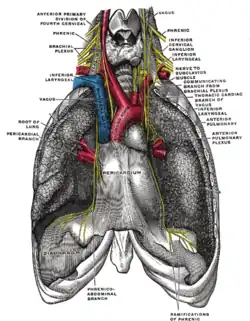

| O nervo frênico e suas relações com outros nervos. | |

O nervo frênico é um nervo que se origina no pescoço (C3-C5) e passa entre o pulmão e o coração para alcançar o diafragma. É importante para a respiração, pois ele passa as informações motoras para o diafragma e recebe informações sensoriais do mesmo. Existem dois nervos frênico, um esquerdo e um direito.

Possui fibras nervosas simpáticas, motoras e sensoriais.[2] Estes nervos fornecem a única fonte motora do diafragma, assim como a sensação do tendão central. No tórax, cada nervo frênico provê para a pleura mediastinal e o pericárdio.

O nervo frênico desce obliquamente com a veia jugular interna através do escaleno anterior, para a camada pré-vertebral da fáscia cervical profunda e as artérias cervical transversa e supraescapular. À esquerda, o nervo frênico cruza para a primeira parte da artéria subclávia. À direita, encontra-se na parte anterior do músculo escaleno e cruza para a segunda parte da artéria subclávia. Em ambos os lados, o nervo frênico segue posterior a veia subclávia conforme ela entra no tórax, onde ela segue anterior para a raiz do pulmão e entre o pericárdio fibroso e da face mediastinal da pleura parietal.[1]

- O nervo frênico direito passa sobre a artéria braquiocefálica, posterior à veia subclávia e então atravessa a raiz do pulmão direito anteriormente, em seguida deixando o tórax, passando através da abertura do hiato da veia cava no diafragma no nível de T8. O nervo frênico direito passa sobre o átrio direito.

- O nervo frênico esquerdo passa sobre o pericárdio do ventrículo esquerdo e perfura o diafragma separadamente.

As artérias e veias pericardiacofrênicas viajam com seus respectivos nervos frênico.

Ambos estes nervos fornecem fibras motoras para o diafragma e fibras sensoriais para o pericárdio fibroso, cápsula de glisson,[5] pleura mediastinal, e o peritônio diafragmático. O frênico supre toda a parte motora do músculo diafragma, o frênico direito a cúpula direita e o esquerdo a cúpula esquerda, e a parte sensitiva da região central desse músculo. Supre a pleura mediastinal e o pericárdio. A total dependência motora do músculo diafragma desse nervo o torna extremamente importante, visto que o músculo é o principal responsável pelo movimento de inspiração.[2] Se divide em 3 ramos, anterior, posterior e lateral.

Secção transversal do tórax, mostrando as relações das artérias pulmonares.

Secção transversal do tórax, mostrando as relações das artérias pulmonares. -